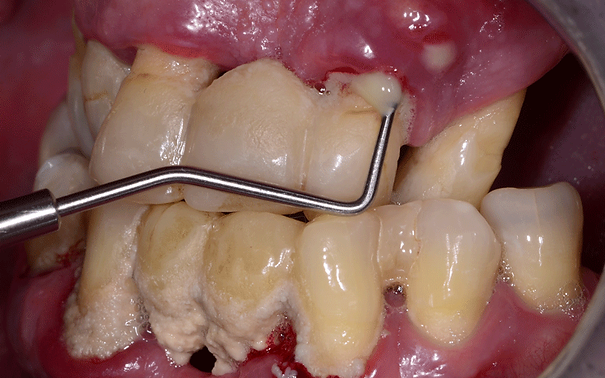

W badaniu podczas zapalenia dziąseł obserwuje się zaczerwienienie, obrzęk dziąseł oraz krwawienie występujące podczas szczotkowania, nitkowania zębów lub delikatnego badania sondą peridontologiczną.

Dlatego sonda periodontologiczna to najważniejszy instrument na tacy zabiegowej higienistki.

Służy do oceny:

- głębokości kieszeni przyzębnych,

- grubości dziąsła,

- pomiaru recesji dziąsłowej, utraty przyczepu,

- badania kamienia poddziąsłowego

- oraz obliczania parametrów zapalenia dziąseł – wskaźników.